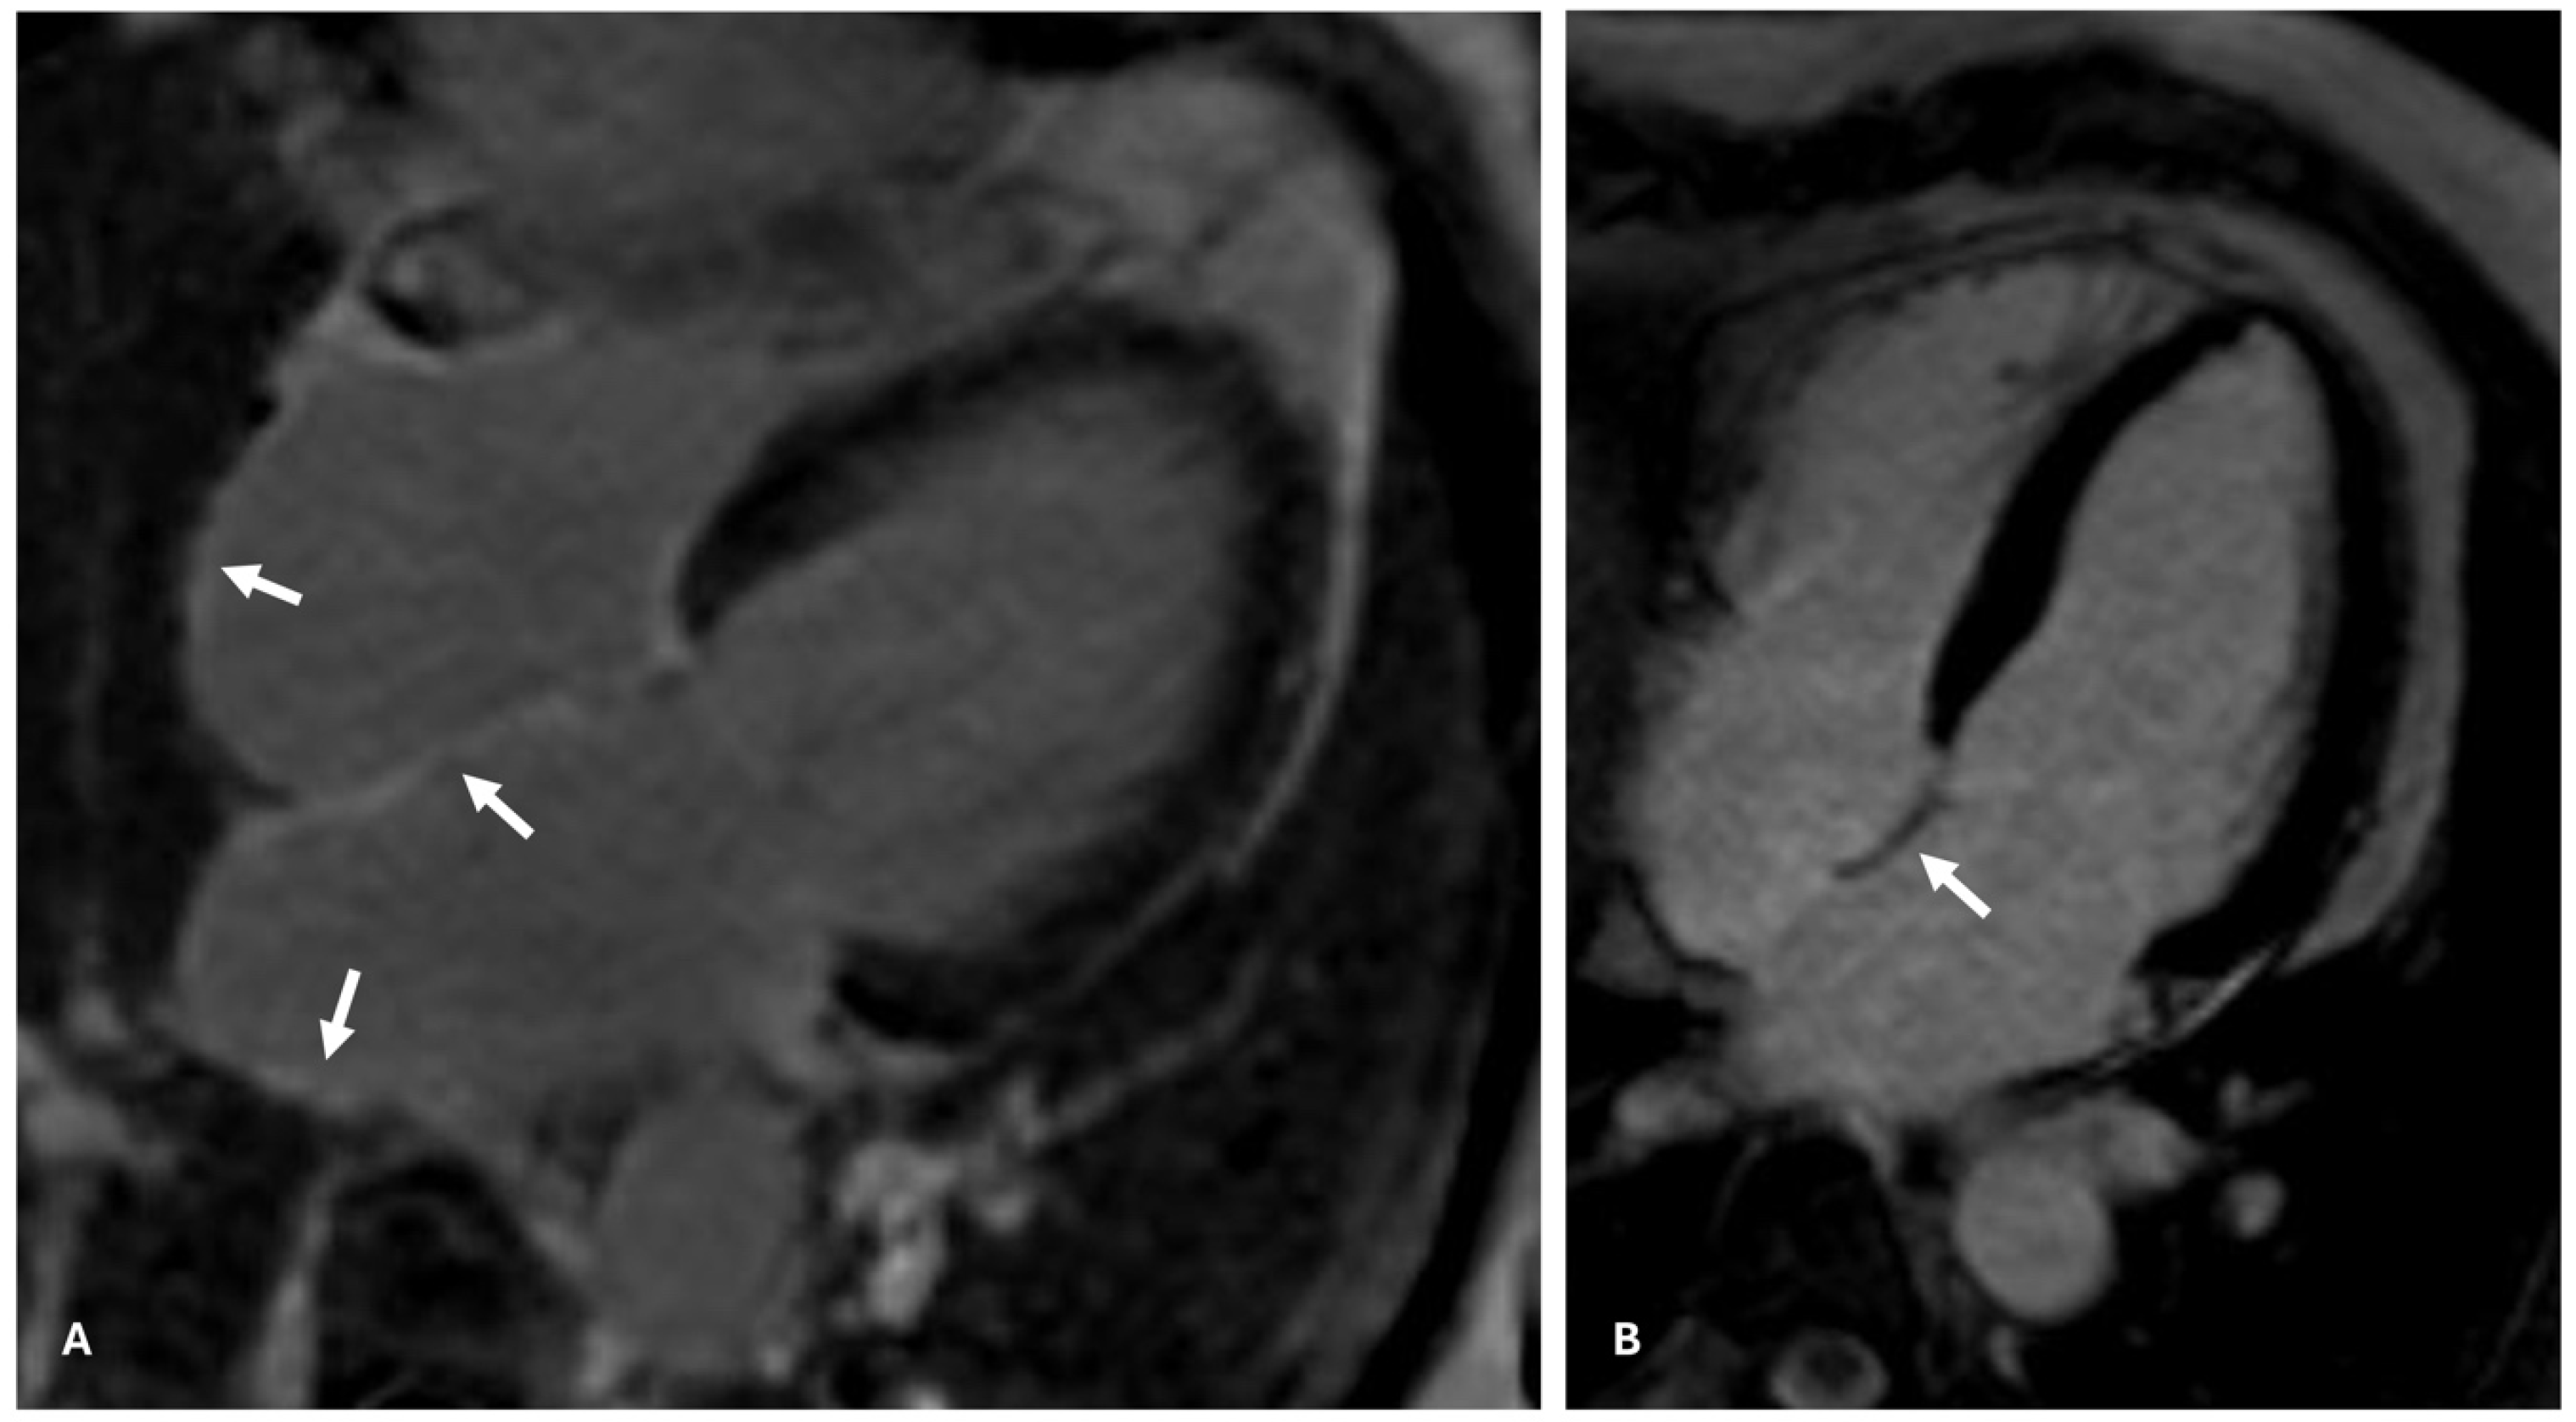

4. Atrial CMR Imaging for LA Fibrosis Evaluation: A New Frontier

7. Limitations of DE-CMR in Detecting Atrial Fibrosis